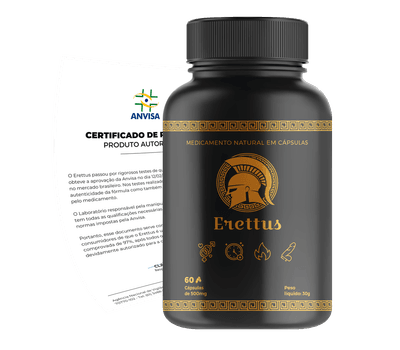

NOVA FÓRMULA 100X MAIS POTENTE

O ERETTUS É A SOLUÇÃO PERMANENTE PARA VOCÊ!

Tratamento 100% natural capaz de eliminar a Disfunção Sexual, aumentar o Vigor e recuperar o Desempenho nas relações. Aprovado pela ANVISA.

A fórmula exclusiva presente no Erettus consiste na junção ultra-concentrada com os 8 Melhores Ativos Naturais que quando unidos, são capazes de eliminar todos os tipos de Disfunção Sexual que você enfrenta! 2 Cápsulas ao dia farão você aumentar seu Vigor, Potência e Desempenho nas relações Sexuais.

O ERETTUS E UM COMPOSTO NATURAL LIBERADO PELA ANVISA!

O Erettus é um produto que atende a todos os requisitos estabelecidos pela Agência Nacional de Vigilância Sanitária (Anvisa) para a venda no Brasil.

O Erettus passou por rigorosos testes de qualidade e segurança, e obteve a aprovação da Anvisa para ser comercializado no mercado brasileiro. Portanto, os consumidores podem ter a tranquilidade de que o Erettus é um produto seguro e de alta qualidade.